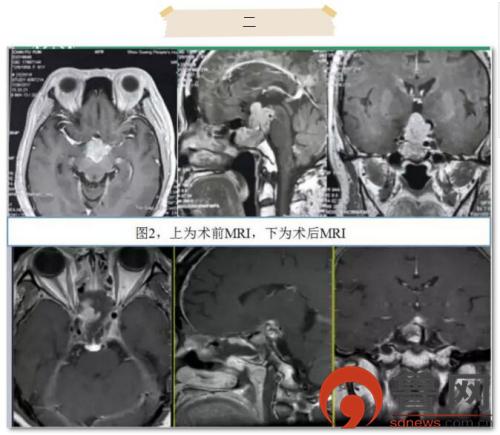

患者2为61岁老年女性,分别于2004年和2016年行两次开颅垂体瘤切除术,此次主诉视力视野障碍来诊。因肿瘤挤压视神经严重,患者入院时几乎失明。患者在院外已行两次开颅手术,此次对再次开颅手术有抵牾。术前科室讨论认为肿瘤主要位于鞍上及第三脑室,侵犯脑干,手术的主要难点为打开鞍隔后的脑脊液漏修补及完全切除累及上斜坡的肿瘤。术中采取扩大蝶鞍入路,全切鞍内肿瘤后打开鞍隔,磨除鞍背骨质,保护环窦、基底窦,进一步探查见肿瘤黏连基底动脉、后交通动脉、动眼神经,并与脑干黏连,内镜下切除完全(图2)。后取自体阔筋膜、肌肉、脂肪,联合止血材料和生物蛋白胶使用“三明治”法修补鞍底。麻醉清醒即刻患者诉视力恢复,无神经功能缺失,术后放置腰大池引流2周,拔除后未再出现脑脊液鼻漏,患者顺利出院。